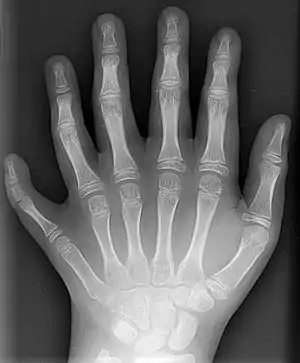

دو نوع از تصاویر حاصل از پرتونگاری در تصویربرداری پزشکی مورد استفاده قرار میگیرد؛ پرتونگاری تجسمی (به انگلیسی: Projection Radiography) و فلوروسکوپی (به انگلیسی: Fluoroscopy). با وجود مقطع نگاریهای سه بعدی (به انگلیسی: 3D Tomography) پیشرفته کنونی، این روشهای دوبعدی همچنان کاربرد گستردهای دارند. زیرا کم هزینه ترند، از رزولوشن بالایی برخوردار هستند و بسته به کاربرد از تشعشع کمتری برخوردارند. در این روش تصویرگری با استفاده از پرتو پرتو ایکس تصویر به وجود میآید. در حقیقت این روش پیشگام تصویرگری در پزشکی مدرن میباشد.